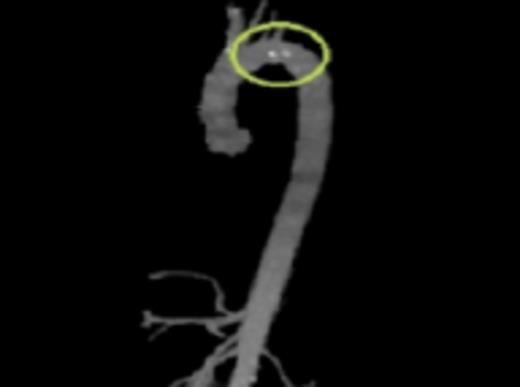

CTA reconstruction highlighting the floating plaques distal to the Left Subclavian artery takeoff

Initial workup included a transesophageal echocardiogram (TEE) which showed a 0.8cm × 0.9cm highly mobile plaque just distal to the take-off of the left subclavian artery. CT angiography (CTA) was then performed to further delineate the anatomy and to evaluate for the possibility of endovascular stent graft placement. CTA showed a thoracic aortic intraluminal filling defect which represented a small area of clot within an atherosclerotic plaque. The CTA also demonstrated an area of decreased attenuation on the upper anterior portion of the spleen consistent with an older splenic infarct.

Diagnostic aortic angiography demonstrating darkening distal to the left subclavian possibly representing plaque. Image prior to stent deployment